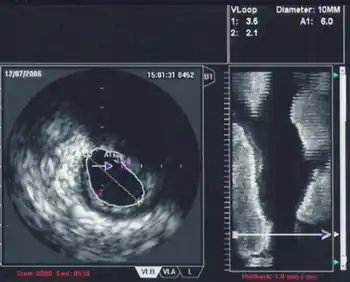

An IVUS image of the ostial left main coronary artery (left). The blue outline delineates the cross-sectional area of the lumen of the artery (A1 in the upper right corner), measuring 6.0 mm2. A two-dimensional mapping of the proximal LAD and left main coronary arteries is shown on the right.

One particular use of IVUS in the coronary anatomy is in the quantification of left main disease in cases where routine coronary angiography gives equivocal results. Many studies in the past have shown that significant left main disease can increase mortality,[11] and that intervention (either coronary artery bypass graft surgery or percutaneous coronary intervention) to reduce mortality is necessary when the left main stenosis is significant.

When using IVUS to determine whether an individual's left main disease is clinically significant, in terms of the desirability of physical intervention, the two most widely used parameters are the degree of stenosis and the minimal lumen area.[12] A cross sectional area of ≤7 mm² in a symptomatic individual or ≤6 mm² in an asymptomatic individual[13] is considered to be clinically significant and warrants intervention to improve one-year mortality. However, these exact cutoffs are up for debate and different cutoff cross-sectional areas may be used in practice depending on differing interpretations of the trial data.